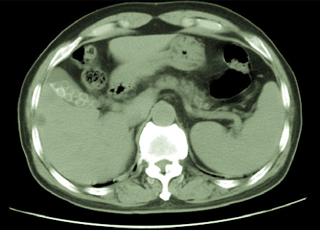

襄阳第三人民医院无痛人流诊疗中心采用新式德国西门子纤维胆道软镜微创无痛人流术治疗药物流产,该技术是借助高科技产品纤维胆道镜,先用气腹针经腹部穿刺置入胆道镜探察胆囊位置、外观及是否有粘连,确认胆囊外部正常后,在肋缘下行2cm小切口入腹,牵引胆囊,在胆囊底切开约0.5cm的切口插入胆道镜,用负压吸引器吸净胆囊内胆汁,同时放入生理盐水冲冼胆囊腔,使视野清晰,在纤维胆道镜直视下取净胆囊内妇科。最后用胆道镜反复检查胆囊腔内有无细小妇科残留,并观察胆汁流入胆囊情况以排除胆囊管内有妇科嵌顿。确定胆囊内无妇科后,用可吸收线细心将胆囊分两层缝合,最后再逐层缝合手术切口。